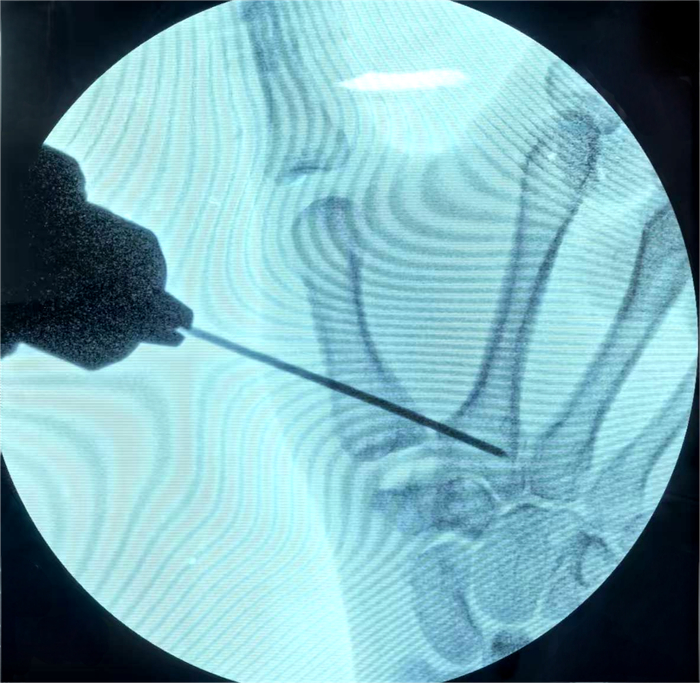

手术由手外科、足踝外科主任医师张诚主刀,副主任医师盖茂杨协助完成。术中仅通过关节两侧各约3毫米的微小切口,借助关节镜精准探查并完成全部操作,整个手术历时仅不到一小时就顺利结束。这种微创术式不仅最大限度减轻了手术创伤,更精准保留了拇指关键功能,契合患者对高质量术后恢复的需求。目前,患者恢复良好,已顺利出院,逐步回归正常生活。